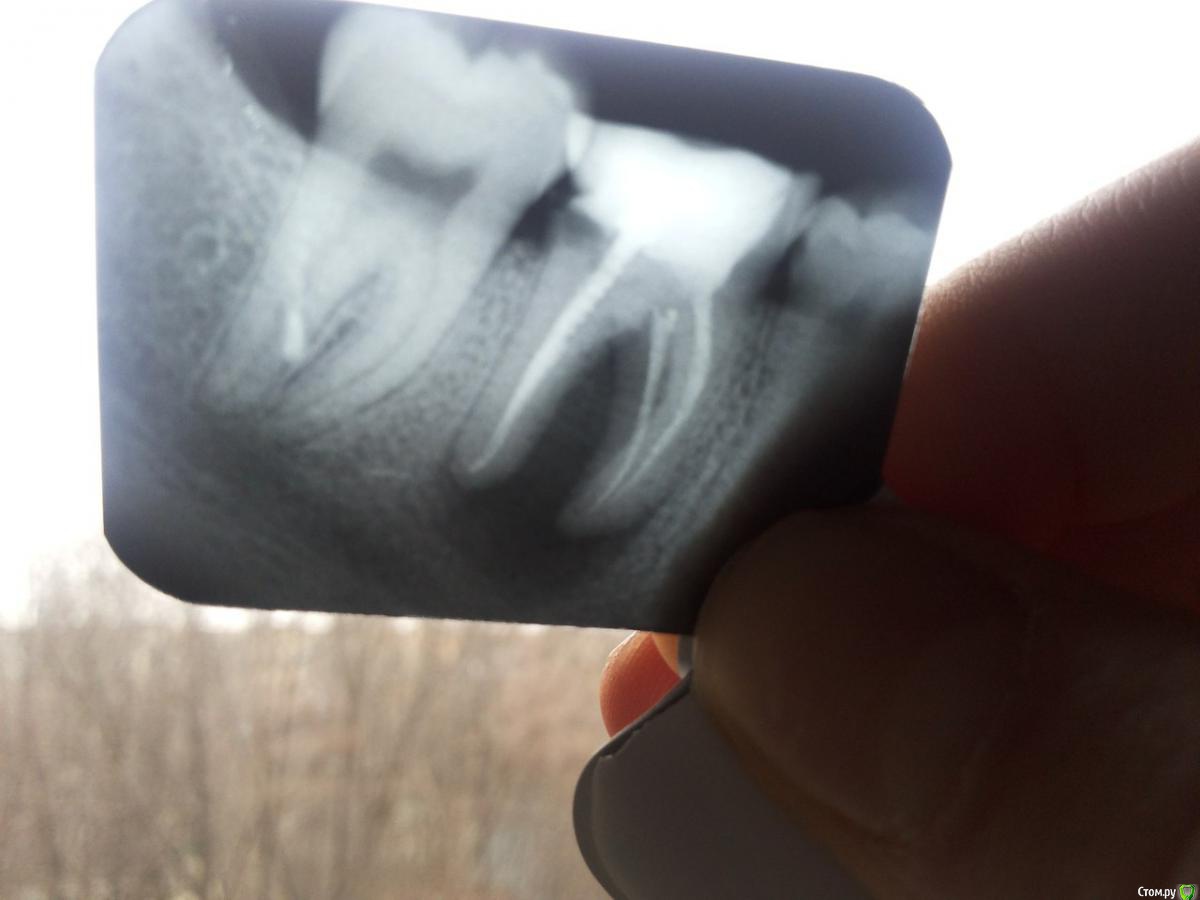

Lilit11 Опубликовано 26 марта, 2016 Поделиться Опубликовано 26 марта, 2016 Здравствуйте. Скажите пожалуйста, зуб подлежит только удалению, или ещё возможно его спасти? Ссылка на комментарий

red_butler Опубликовано 26 марта, 2016 Поделиться Опубликовано 26 марта, 2016 если судить только по снимку, то можно полечить. Но нужен очный осмотр, ревизия и квалифицированный врач. 1 Ссылка на комментарий

horreodor Опубликовано 26 марта, 2016 Поделиться Опубликовано 26 марта, 2016 я соглашусь что нужен очный осмотр, но с моей точки зрения шансы на его спасение очень малы... Ссылка на комментарий

krokomot Опубликовано 26 марта, 2016 Поделиться Опубликовано 26 марта, 2016 Шансы невелики Ссылка на комментарий

Lilit11 Опубликовано 26 марта, 2016 Автор Поделиться Опубликовано 26 марта, 2016 (изменено) Специалисты, объясните пожалуйста, почему его вряд ли получится сохранить, и, почему только удаление?Стоматолог, к которому я обратилась с рентгеном, сказала, что только удаление, и, объяснила это тем, что мой организм воспринимает мой зуб как инородное тело, а дальше я её не совсем поняла, т.к. объясняла она не очень вразумительно. Всё таки не очень хочется остаться без зуба, если есть хоть небольшая возможность, его спасти. Проблема усугубляется ещё и тем, что я не знаю к кому идти. Если здесь есть врачи или пациенты из Днепропетровска, посоветуйте, с кем можно проконсультироваться? Изменено 26 марта, 2016 пользователем Lilit11 Ссылка на комментарий

shishok Опубликовано 26 марта, 2016 Поделиться Опубликовано 26 марта, 2016 Мне кажется или там трещина дистального корня? Ссылка на комментарий